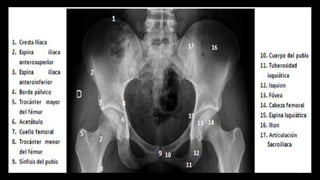

RX

• PIRMERA TECNICA SOLICITADA

– TRAUMATICA

– DEGENERATIVA

– INFLAMATORIA

– TUMORAL

• SOSPECHA DCC

AP